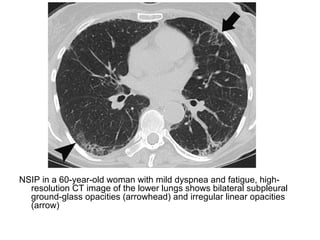

NSIP in a 60-year-old woman with mild dyspnea and fatigue, high-

resolution CT image of the lower lungs shows bilateral subpleural

ground-glass opacities (arrowhead) and irregular linear opacities

(arrow)